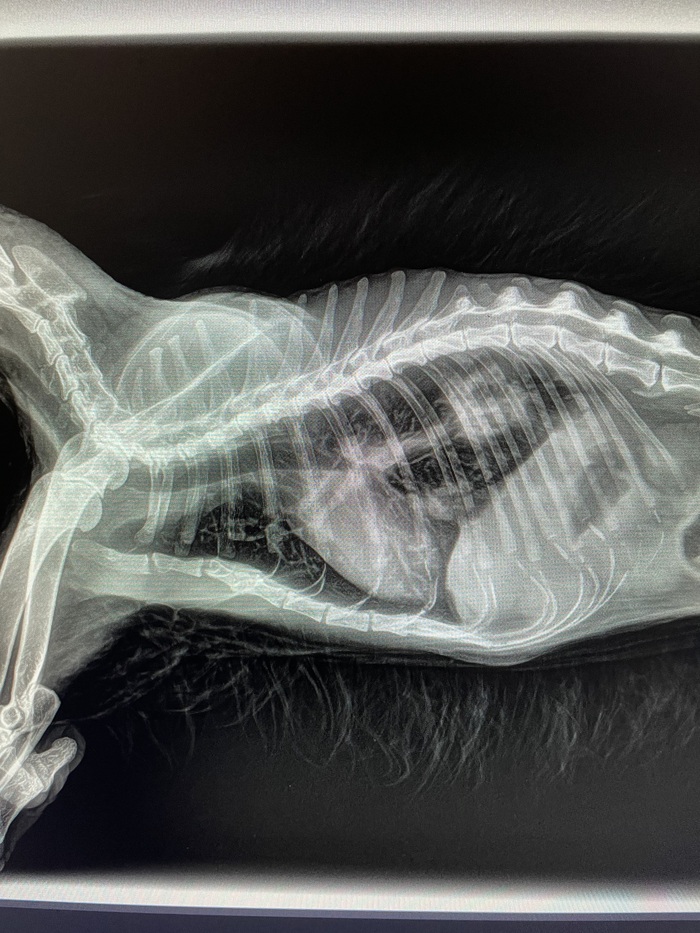

Дано: возрастная кошка с длительным ринитом.

Пришли на прием 13.10 с формулировкой «гноится глазик». Я увидел их 14.10 и всё же уговорил пойти на кт, а там абсцесс за левым глазом, фронтит (забиты и лобные пазухи, и носовые ходы).

После проводим фронтотомию - по сути, бурим дырку в лобную пазуху для промывания и вымывания всего скопившегося гноя.

Промыв всё большим количеством тёплого стерильного физ.раствора, зашиваем всё. Плюсом удаляем назофарингеальный полип.